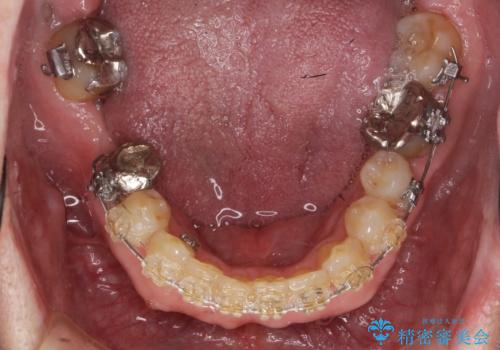

矯正治療後、右下のインレーブリッジおよび左下の銀歯のやりかえを行なっています。

右上の八重歯は、右上の奥歯を矯正用ミニスクリューを用いて遠心移動を行い解消しました。

下の前歯はIPR(エナメル質を薄く削り歯を小さくする処置)を行なっています。